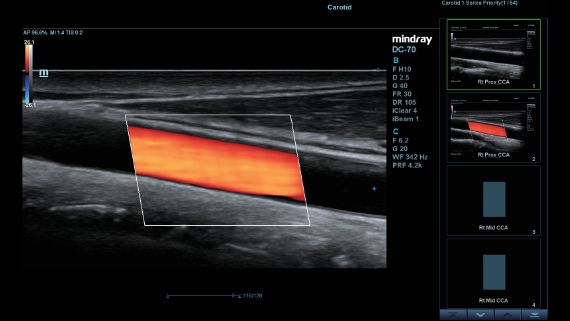

DC-60

Dedicated Care for ECHO

As an all-around partner, DC-60 ECHO with X-Insight devotes to provide a comprehensive solution to help you manage all-aspect daily clinical practice with ease and certainty.

Based on the deep insights of customer needs, the DC-60 ECHO with X-Insight is designed to deliver high efficiency with precision imaging, which is empowered by eXpress Clarity, eXceptional Intelligence and eXceeding Experience.